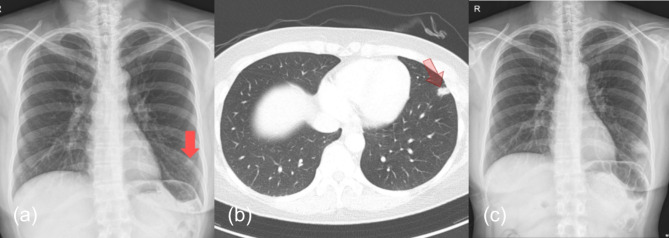

Case presentation: A 46-year-old healthy woman was incidentally found to have a 1.3-cm pulmonary nodule in the left anterior basal segment during a routine health examination, with no symptoms or significant medical history. Initial CT imaging raised suspicions of T1a lung cancer. Subsequent endobronchial ultrasound transbronchial lung biopsy and transbronchial lung cryobiopsy revealed granulomatous inflammation. Tests for tuberculosis and NTM, including acid-fast bacilli (AFB) smear, mycobacterial culture, and PCR for Mycobacterium tuberculosis and NTM, were negative. Following the biopsies, chest X-rays showed an enlarged shadow at the lesion, suggesting necrosis after cryobiopsy. The patient was treated with moxifloxacin, leading to symptom improvement. A final diagnosis of NTM infection, specifically Mycobacterium avium, was confirmed from bronchoalveolar lavage fluid obtained three weeks after the tissue biopsy. Remarkably, at four months post-biopsy, a chest CT scan showed complete resolution of the nodule without additional antimicrobial therapy, suggesting a potential therapeutic effect of cryobiopsy-induced cryoablation.